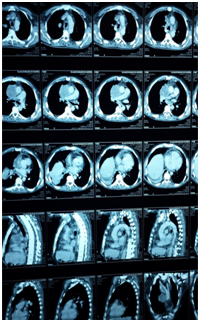

Clinical case

Male 55 years of age, genetic burden to you, dm, heart disease. Tab up to 6 months 5 cigarettes a day for 15 años. PA Starts 4 months myalgia and arthralgia, headache with decubitus, dizziness, dry cough without predominance of time, wheezy, hyperoxia, tired, exhausted, insomnia, lateropulsion, dorsalgia .disfonía ago , dyspnea small efforts, night sweats, back pain, facial edema, lower limb, abominal, upper limb and neck EFTA 90/60, FC 120X MIN, facial edema and neck, even sitting jugular plethora, thoracic venous network, adenomegalia bilateral neck and underarm, edema and abdominal wall members inferiores (Figure 1). He underwent chest CT lung tumor reporting based region right evil-looking, mediastinal tumor with calcifications and data invasion of pericardium and conditioning svcs superior vena cava, mediastinal lymphadenopathy of bilateral hilar groups prevascular (Figure 2) (Figure 3).

Figure 2 Report of CT lung tumor.

Figure 3 Report of CT lung tumor.